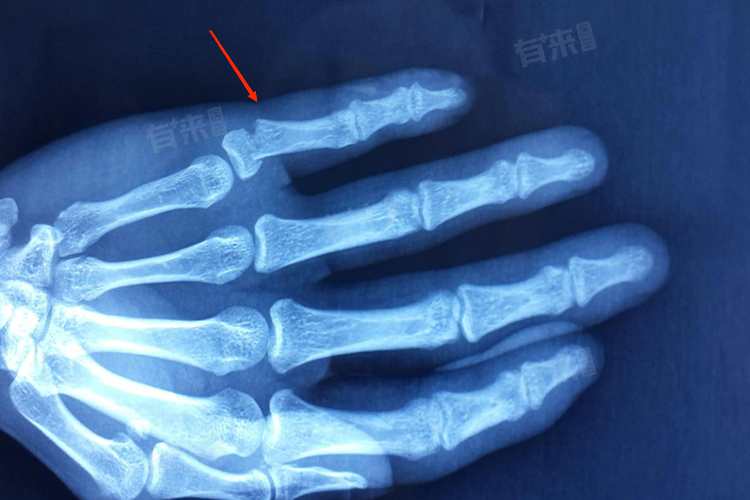

- 如果小手指骨折较为严重,比如出现粉碎性骨折、骨折明显移位、合并神经血管损伤等情况,就有可能被认定为轻伤甚至更严重的损伤级别。粉碎性骨折意味着骨头碎裂成多块,治疗难度较大,恢复时间较长,且可能会对手指的外观和功能产生较大的影响。

- 骨折移位可能会导致手指畸形,影响关节的活动度。神经血管损伤则可能引起手指感觉异常、血液循环障碍等问题,严重的甚至会导致手指功能丧失。